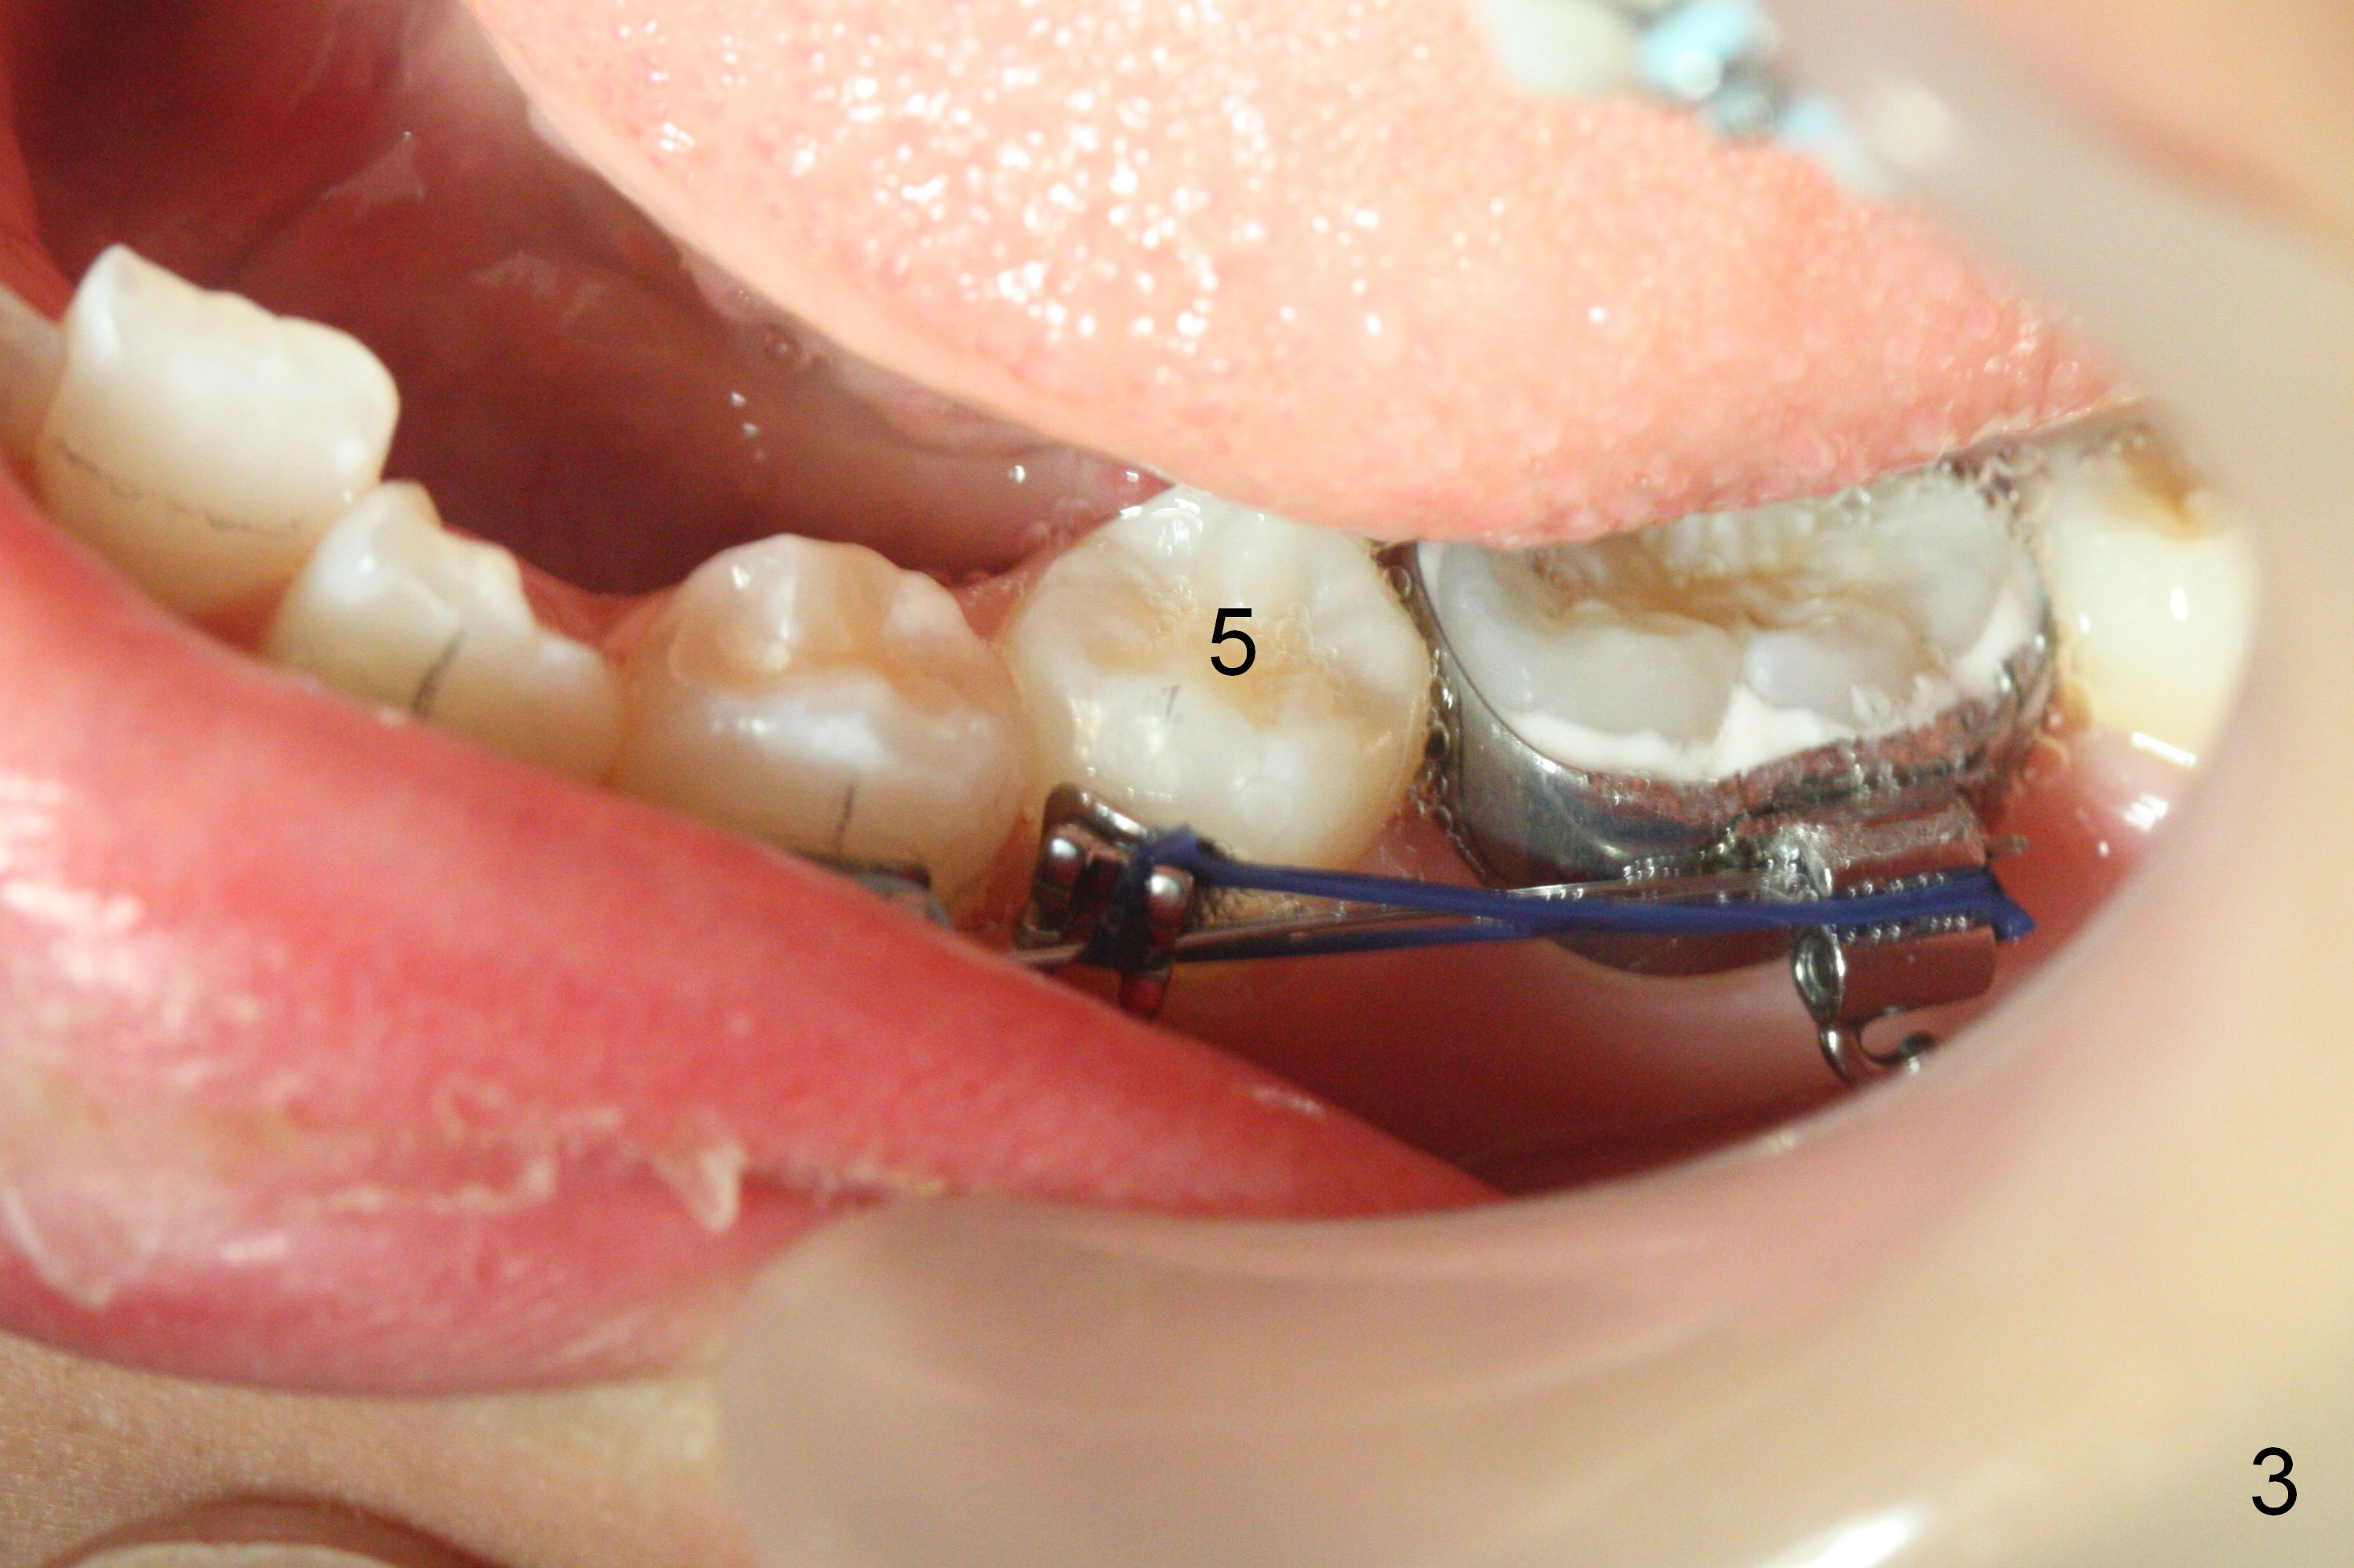

As planned, the peg laterals do not have brackets placed (Fig.2), since their position and shape will be ultimately decided by veneers. Alignment of the lower arch is more severe than that of the upper one, characterized by severe crowding at LR 3 and 4 (Fig.1) and rotation of LL 5 (Fig.3). Oral hygiene does not improve during orthodontic treatment. Impression will be taken prior to debanding. Space is obtained for LL2; brackets are placed at LL2 and 5; 14 niti wire is placed 9 months post banding (Fig.4-6). Orthodontic treatment is terminated prematurely partially due to poor oral hygiene.